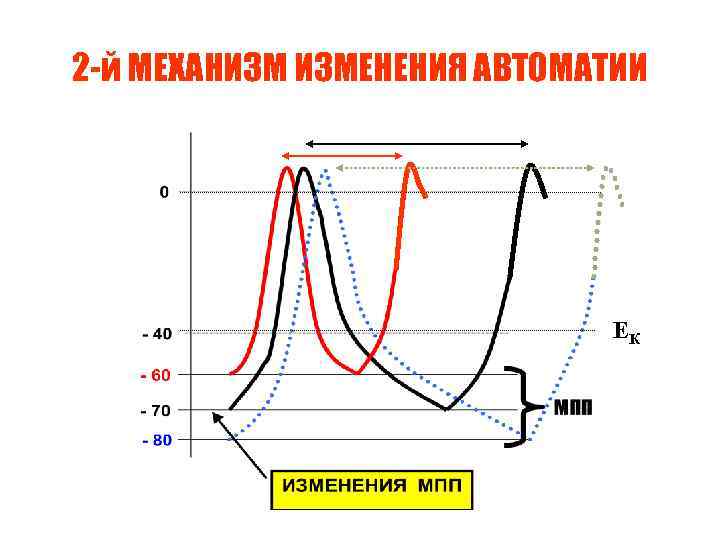

2 -й МЕХАНИЗМ ИЗМЕНЕНИЯ АВТОМАТИИ ЕК

2 -й МЕХАНИЗМ ИЗМЕНЕНИЯ АВТОМАТИИ ЕК